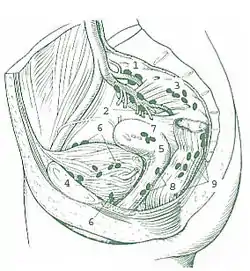

The internal iliac lymph nodes (or hypogastric) surround the internal iliac artery and its branches (the hypogastric vessels), and receive the lymphatics corresponding to the distribution of the branches of it, i. e., they receive lymphatics from all the pelvic viscera, from the deeper parts of the perineum, including the membranous and cavernous portions of the urethra, and from the buttock and back of the thigh. The internal iliac lymph nodes also drain the superior half of the rectum, above the pectinate line.[1][2]

It does not receive lymph from the ovary or testis, which drain to the paraaortic lymph nodes.